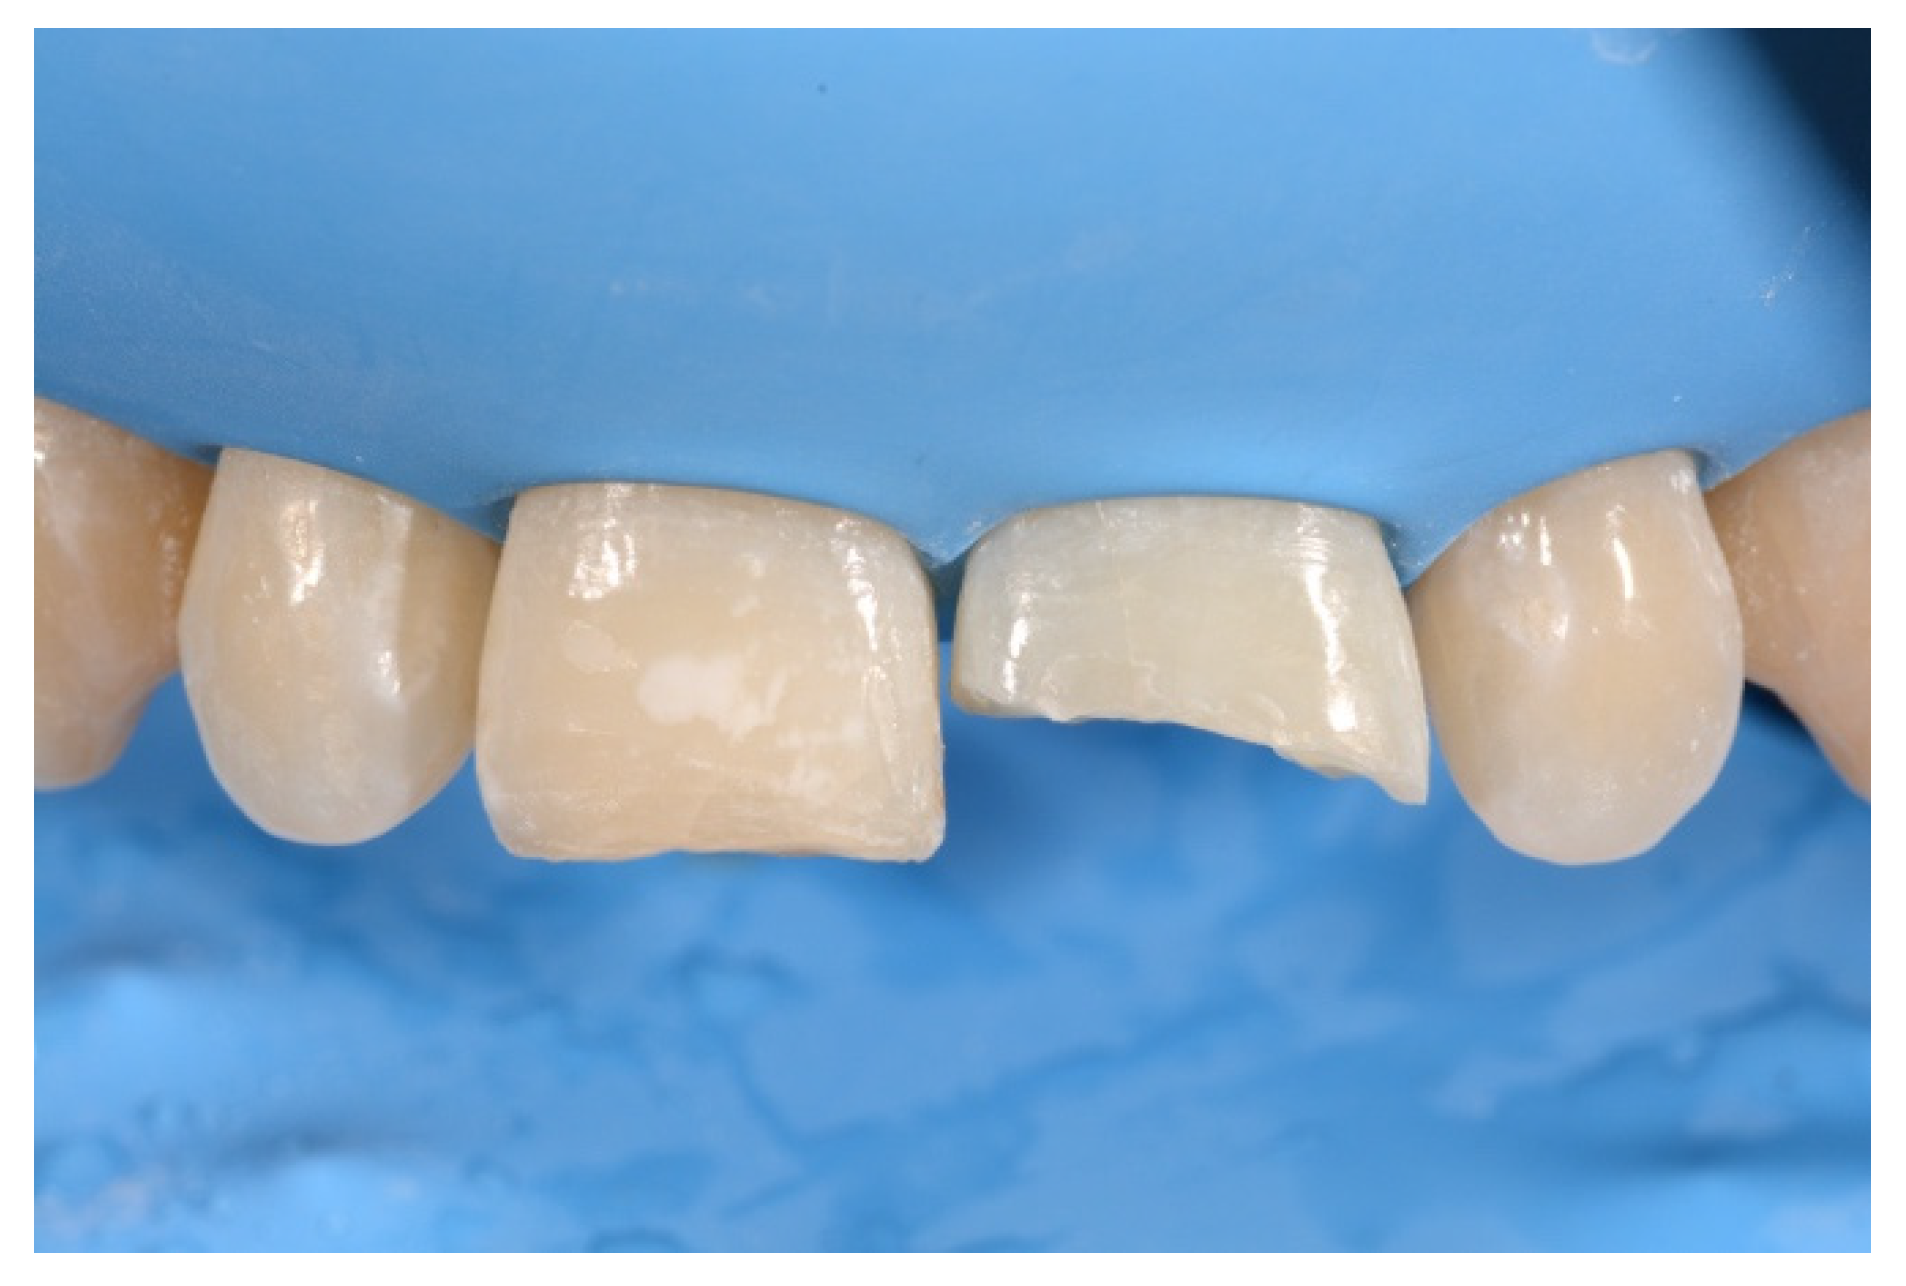

2. Case Presentation